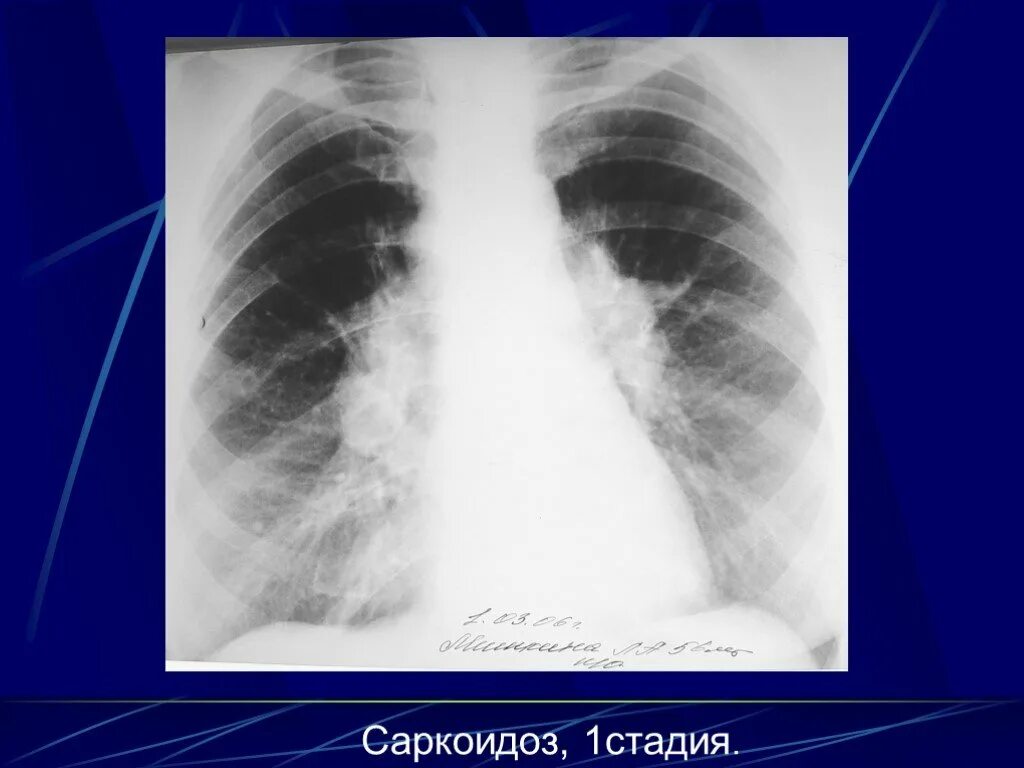

Саркоидоз 1